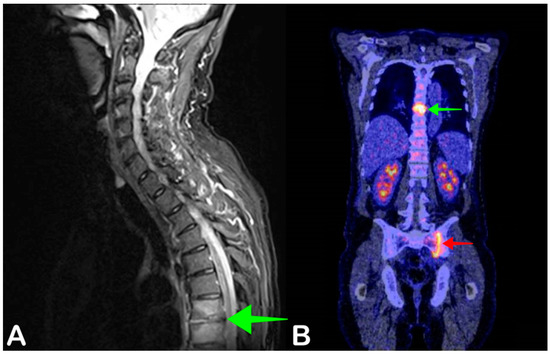

2.5. Spondylodiscitis

- Smids, C.; Kouijzer, I.J.E.; Vos, F.J.; Sprong, T.; Hosman, A.J.F.; De Rooy, J.W.J.; Aarntzen, E.H.J.G.; De Geus-Oei, L.-F.; Oyen, W.J.G.; Bleeker-Rovers, C.P. A comparison of the diagnostic value of MRI and 18F-FDG-PET/CT in suspected spondylodiscitis. Infection 2017, 45, 41–49. [Google Scholar] [CrossRef]

- Altini, C.; Lavelli, V.; Niccoli-Asabella, A.; Sardaro, A.; Branca, A.; Santo, G.; Ferrari, C.; Rubini, G. Comparison of the Diagnostic Value of MRI and Whole Body 18F-FDG PET/CT in Diagnosis of Spondylodiscitis. J. Clin. Med. 2020, 9, 1581. [Google Scholar] [CrossRef]